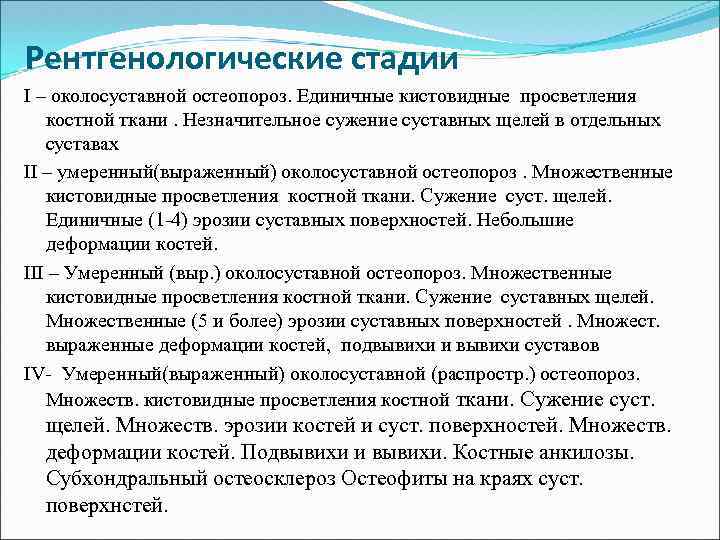

Рентгенологические стадии І – околосуставной остеопороз. Единичные кистовидные просветления костной ткани. Незначительное сужение суставных щелей в отдельных суставах ІІ – умеренный(выраженный) околосуставной остеопороз. Множественные кистовидные просветления костной ткани. Сужение суст. щелей. Единичные (1 -4) эрозии суставных поверхностей. Небольшие деформации костей. ІІІ – Умеренный (выр. ) околосуставной остеопороз. Множественные кистовидные просветления костной ткани. Сужение суставных щелей. Множественные (5 и более) эрозии суставных поверхностей. Множест. выраженные деформации костей, подвывихи и вывихи суставов ІV- Умеренный(выраженный) околосуставной (распростр. ) остеопороз. Множеств. кистовидные просветления костной ткани. Сужение суст. щелей. Множеств. эрозии костей и суст. поверхностей. Множеств. деформации костей. Подвывихи и вывихи. Костные анкилозы. Субхондральный остеосклероз Остеофиты на краях суст. поверхнстей.

Рентгенологические стадии І – околосуставной остеопороз. Единичные кистовидные просветления костной ткани. Незначительное сужение суставных щелей в отдельных суставах ІІ – умеренный(выраженный) околосуставной остеопороз. Множественные кистовидные просветления костной ткани. Сужение суст. щелей. Единичные (1 -4) эрозии суставных поверхностей. Небольшие деформации костей. ІІІ – Умеренный (выр. ) околосуставной остеопороз. Множественные кистовидные просветления костной ткани. Сужение суставных щелей. Множественные (5 и более) эрозии суставных поверхностей. Множест. выраженные деформации костей, подвывихи и вывихи суставов ІV- Умеренный(выраженный) околосуставной (распростр. ) остеопороз. Множеств. кистовидные просветления костной ткани. Сужение суст. щелей. Множеств. эрозии костей и суст. поверхностей. Множеств. деформации костей. Подвывихи и вывихи. Костные анкилозы. Субхондральный остеосклероз Остеофиты на краях суст. поверхнстей.